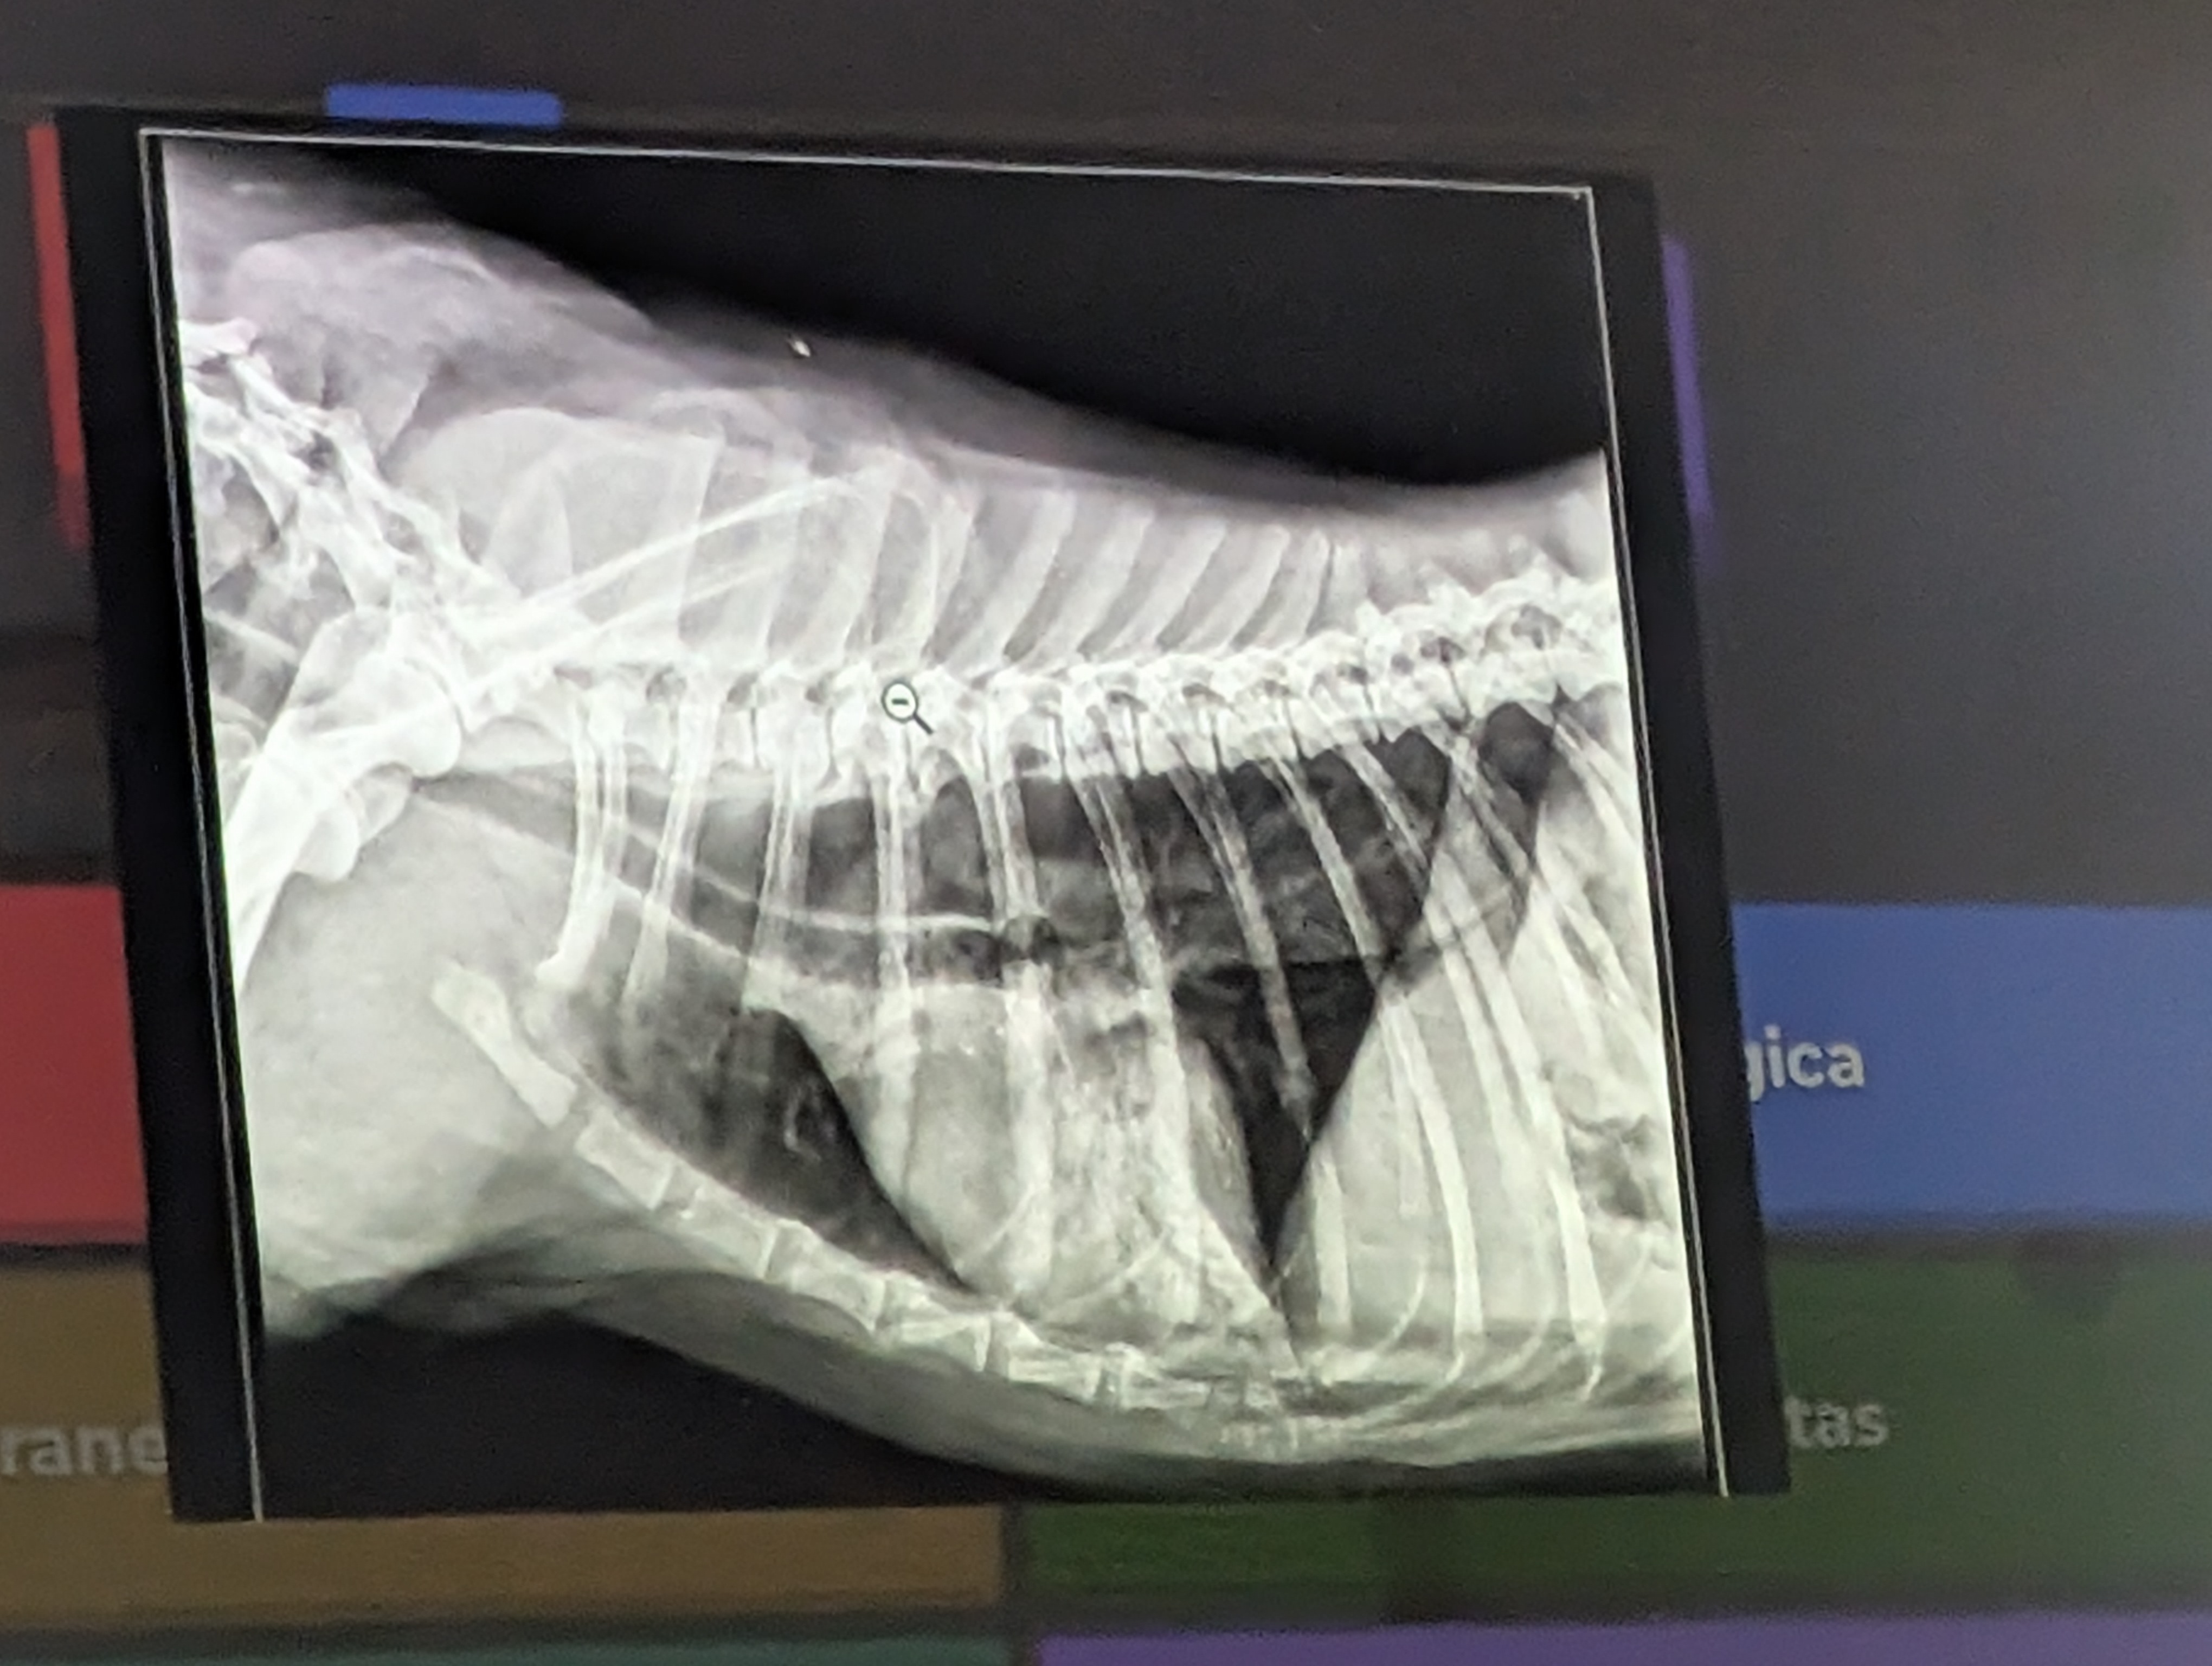

12) Varias respuestas correctas

- Dilatación esofagica (vemos corazon y traquea desplazados)

- Broncograma aereo (Visualización de bronquios llenos de aire dentro de una consolidación pulmonar, se ven menos radioopacos que el pulmon)

- Patron alveolar (Radiográficamente, se manifiesta como un aumento de la opacidad (zonas blancas) de aspecto algodonoso y con márgenes mal definidos.)